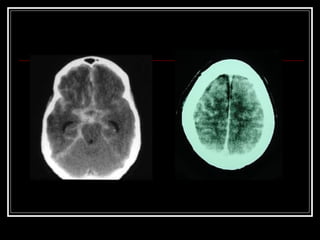

Lesão Axonal Difusa

 caracterizada por coma prolongado, é uma

lesão de alta velocidade com estiramento ou

chacoalhamento do tecido cerebral, com

mortalidade de 33% e, nos casos mais severos,

de 50%, geralmente causada por aumento da

pressão intracraniana secundária ao edema

cerebral, causado por mini hemorragias

(petequias) em substancia branca. O

diagnóstico é realizado em pacientes em coma,

com posturas de descerebração o decorticação.

Lesão Axonal Difusa caracterizada por coma prolongado, é uma lesão de alta velocidade com estiramento ou chacoalhamento do tecido cerebral, com mortalidade de 33% e, nos casos mais severos, de 50%, geralmente causada por aumento da pressão intracraniana secundária ao edema cerebral, causado por mini hemorragias (petequias) em substancia branca. O diagnóstico é realizado em pacientes em coma, com posturas de descerebração o decorticação.